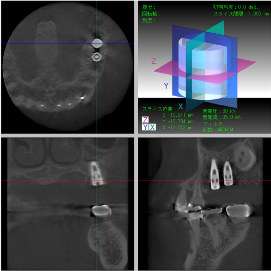

骨再生した箇所にインプラントを埋入します。

CTで治療計画を綿密に練ったうえで行いました。

インプラント埋入

インプラント埋入後のレントゲン画像です。